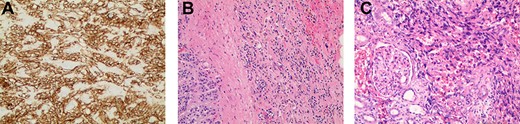

Left renal mass measuring 11 × 9 × 7cm in transverse (left) and coronal (right) planes.

A 52-year-old, previously healthy, Caucasian male presented to the emergency department (ED) with chief complaints of gross hematuria, abdominal pain, vomiting, diarrhea and left flank pain for 3 days. He had neither family history of cancer nor history of exposure to ionizing radiation, arsenic, thorium dioxide or vinyl chloride. He reported exposure to chemical tankers 10 years prior and had recent occupational exposure to paint-thinning agents. Urinalysis on admission showed large blood with later cytology significant for atypical epithelioid cells concerning for neoplasm of the kidney or bladder. Subsequent contrast-enhancedcomputed tomography (CT) of the abdomen revealed an 11-cm left renal mass, 2-cm para-aortic lymphadenopathy and possible invasion of the tail of the pancreas (Fig. 1). He was then referred to urology for evaluation and to discuss treatment options.